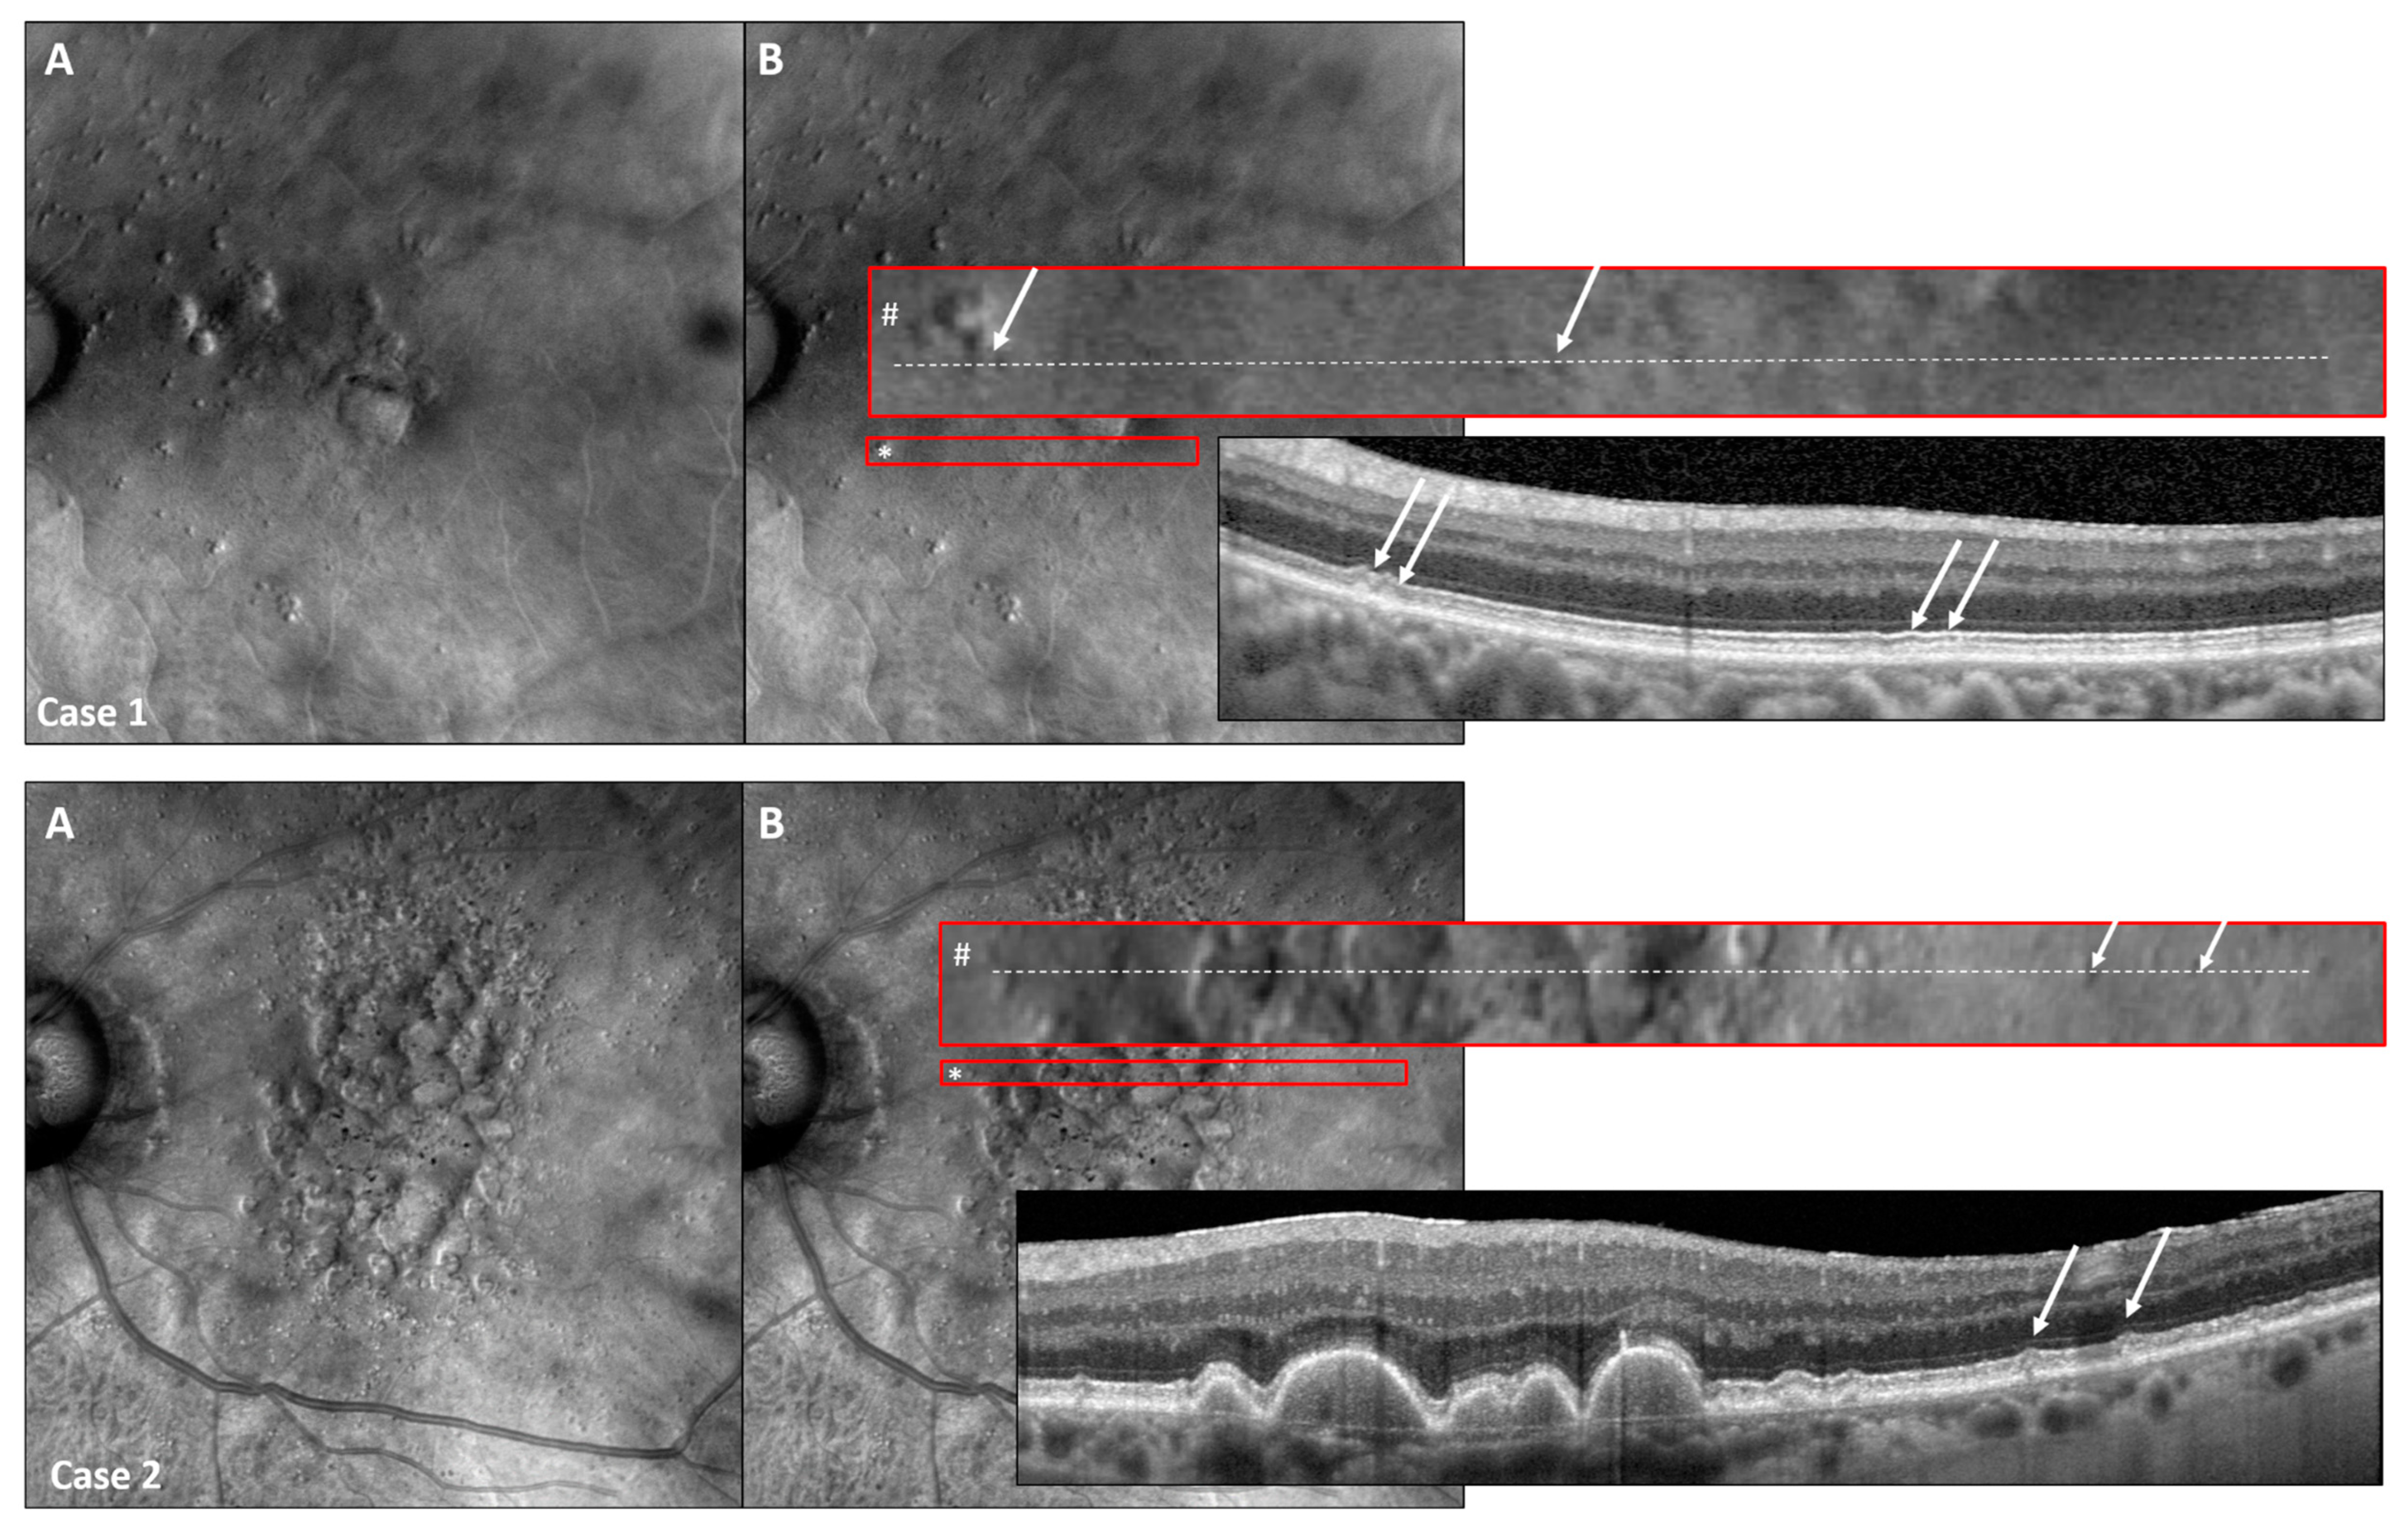

Using the Retro mode, we were able to detect even the early stages of SDDs (stage 1, as defined by Zweifel et al. [7]), with SDD stages confirmed in SD-OCT imaging (Figure 6).

Figure 6.

Retro mode detects early SDD stages. Two representative study eyes presenting with early SDD stages detectable with Retro mode and high-resolution SD-OCT imaging (High-Res OCT). Consider the Retro mode image (A) with the red encircling the original size of the displayed area (*) as well as the enlarged red-encircled (#) area of interest shown in image (B). The exact location of the corresponding OCT scan is shown as a white-dashed line in the enlarged red rectangle (#). As SDDs were detectable in both patient examples, Retro mode imaging is capable of detecting even slight subretinal alterations representing the early stages of SDD (white arrows) [7].